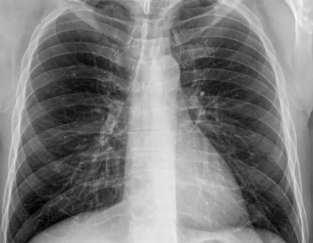

- 진단 기준: 폐기능 검사를 통해 폐활량과 폐쇄 정도를 평가하며, FEV1(1초간 강제호기량) 수치를 활용해 병의 심각도를 판별합니다.

- 폐활량 측정: FEV1 수치를 기준으로 평가합니다. 일반적으로 FEV1 수치가 30% 이하로 감소한 경우 심각한 상태로 분류됩니다.